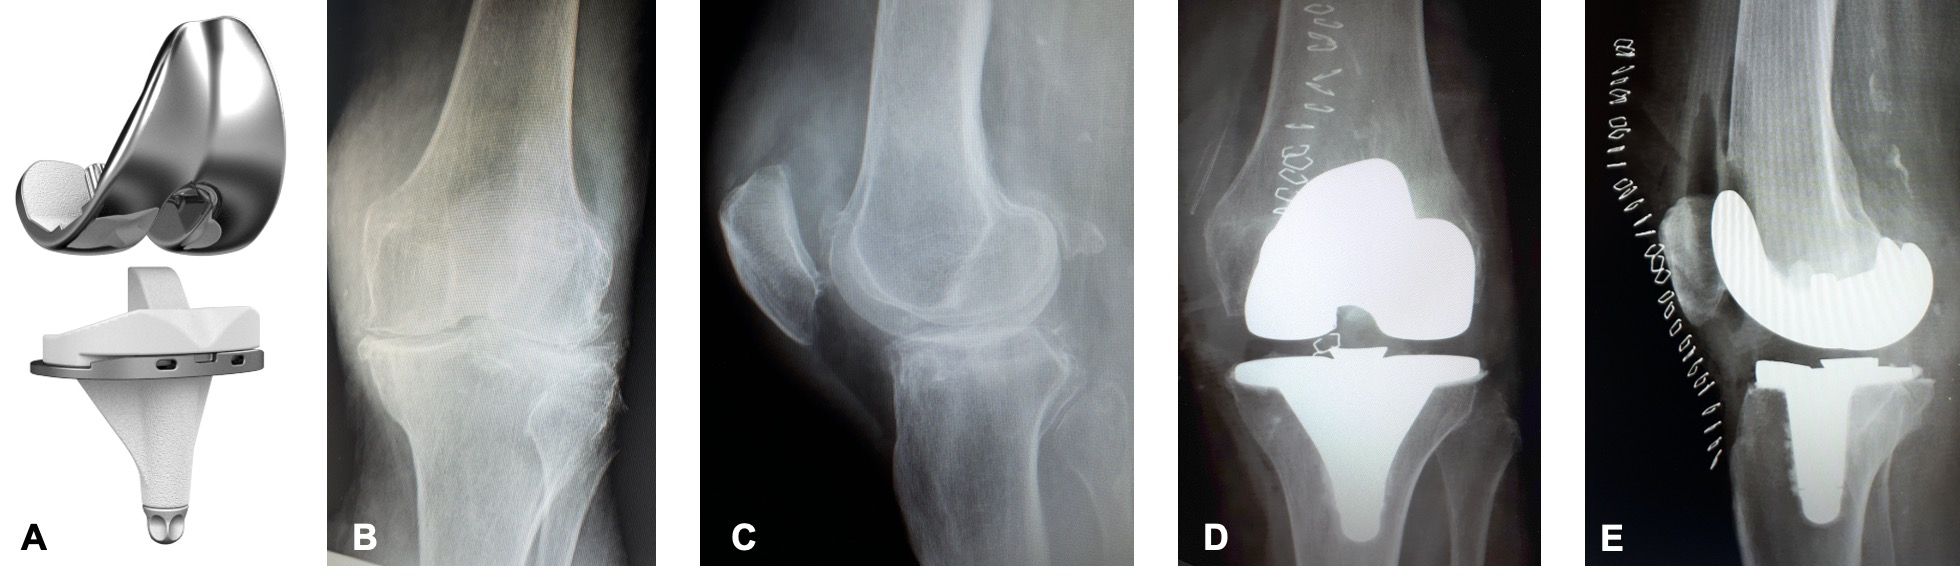

When designing a total knee arthroplasty (TKA), there are two factors that will determine the success of the procedure: implant design and instrumentation. Both dictate the surgical technique, but not all instruments allow any surgical philosophy to be used. The KNEO Group has listed 10 key points for the design of a modern TKA and the choices made when developing the KNEO posterior-stabilized implant (Groupe Lépine, Genay, France).1 Based on these key considerations, the KNEO Group has now developed its own posterior-stabilized fixed-bearing total knee prosthesis (Figure 1) and universal instruments, which allow the surgeon to perform his own technique and surgical philosophy.

The KNEO system comprises 11 sizes of femoral and 11 sizes of tibial components and six heights of polyethylene insert. Each insert is compatible with 5 tibial sizes (nominal size ± two sizes). For the tibial component, the decision was taken to produce an asymmetric anatomical implant that would not only offer the benefits of positioning the implant in external rotation, but also allows for anthropomorphic variations in size ratio between proximal tibia and distal femur on an international market. The femoral trochlea is anatomically shaped, meaning it is sufficiently concave for use without patellar resurfacing, whilst also providing an effective guide for a prosthetic patella. The prosthetic trochlea has a physiological trochlear angle with a raised lateral rim. For patellar resurfacing procedures, the patellar component is fixed using three cemented pegs. In profile, the patellar implant is shaped somewhere between a dome and a ‘Mexican hat’, which does not only create an effective (contactless) guide in the trochlear notch but also to form a wide support base between the trochlear rims and the broad periphery of the patellar implant. The aim of this paper to describe in more details the surgical options and tips and tricks for the universal KNEO instruments.